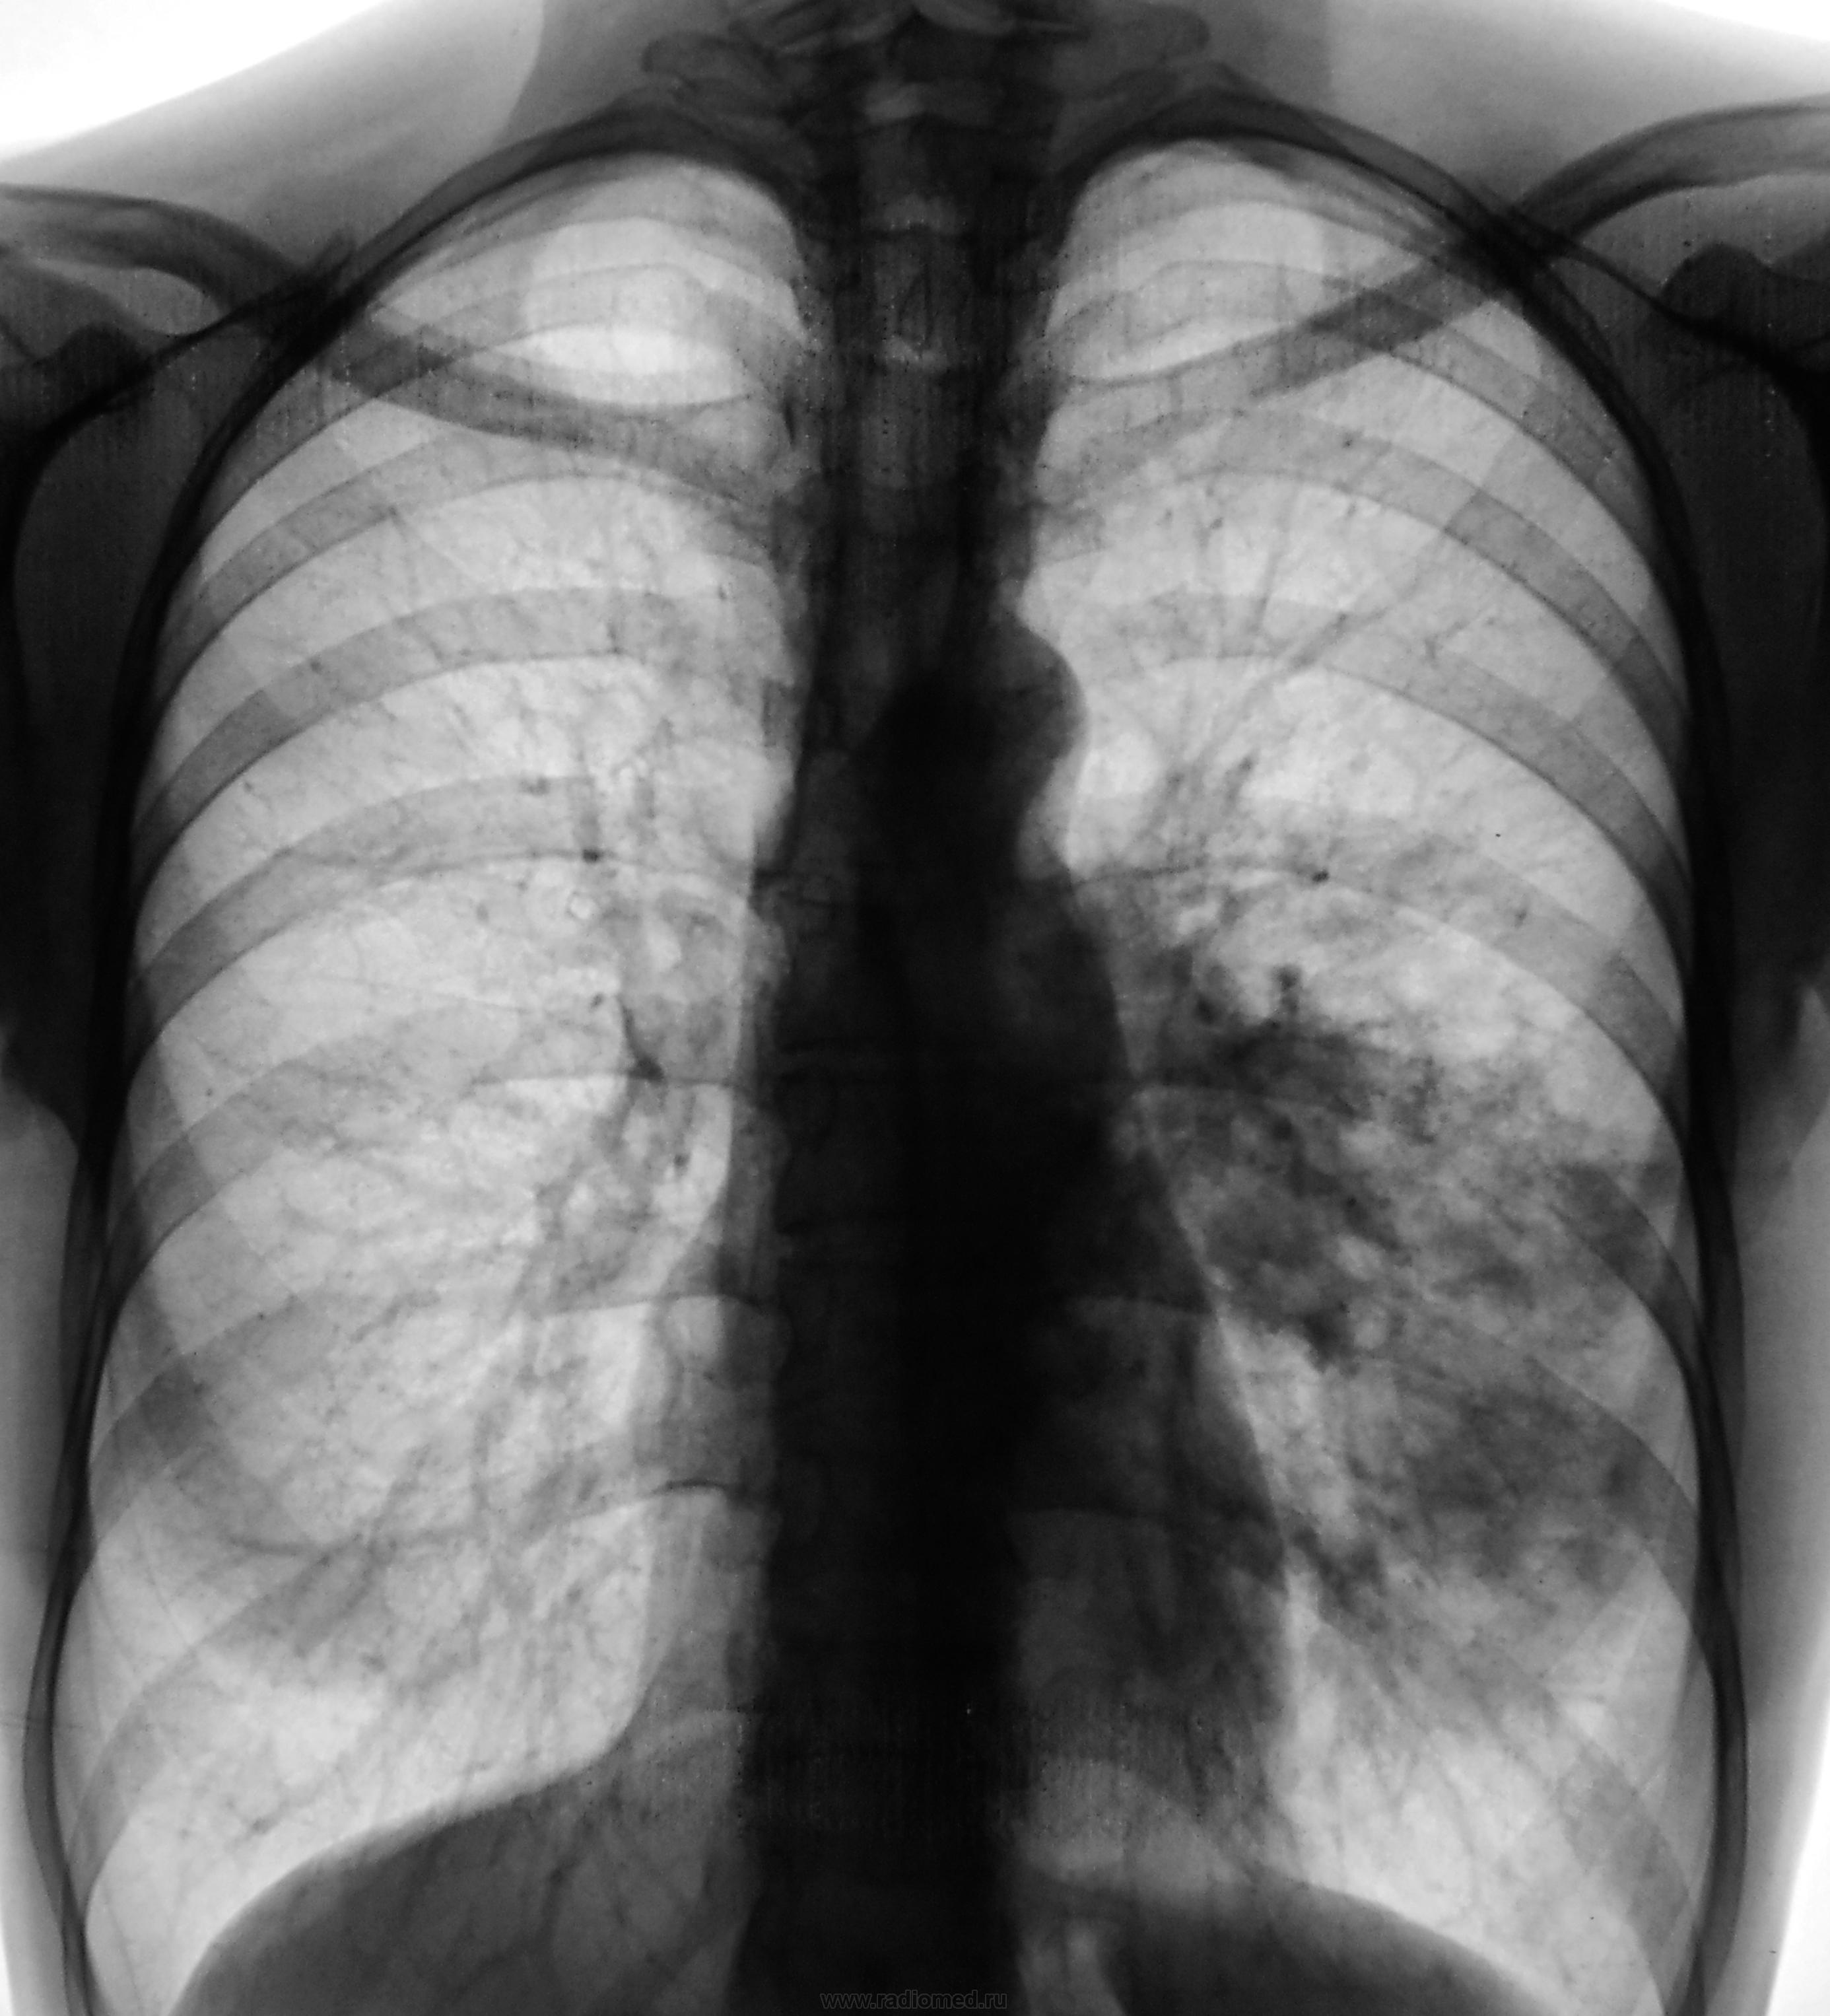

Пол пациента: Мужской пол Тип патологии: Воспалительное заболевание неинфекционной природы Область исследования: Грудная клетка и верхние дыхательные пути Методы исследования: Rg С подозрением на левостороннюю пневмонию пациент направлен на рентгенографию ОГК. https://radiomed.ru/sites/default/files/styles/case_slider_image/public/user/12/2.dscn1380.jpg?itok=9KBXvZ22 ID:27777 Чт, 11/04/2013 - 19:32 #1 maker4ik Не на сайте Был на сайте: 8 лет 7 месяцев назад Зарегистрирован: 19.10.2011 - 17:49 Публикации: 2682 ТБС в 6 Чт, 11/04/2013 - 19:41 #2 Сергей Кузьминов Не на сайте Был на сайте: 1 год 1 неделя назад Зарегистрирован: 06.10.2012 - 15:51 Публикации: 11813 На вершушке слева тоже очаги есть,но до контрольного снимка считал бы пневмонией сегментарнойS6. Чт, 11/04/2013 - 20:35 #3 Nikolas Не на сайте Был на сайте: 1 месяц 3 недели назад Зарегистрирован: 21.12.2010 - 20:37 Публикации: 4559 в S6, 10 левого легкого. Полагаю, что клинико-лабораторные данные подтвердят. Пт, 12/04/2013 - 01:35 #4 Катенёв Валенти... Не на сайте Был на сайте: 7 лет 2 недели назад Зарегистрирован: 22.03.2008 - 22:15 Публикации: 54876 maker4ik wrote: ТБС в 6 А, только для шестерки не многовато? Пт, 12/04/2013 - 18:23 #5 maker4ik Не на сайте Был на сайте: 8 лет 7 месяцев назад Зарегистрирован: 19.10.2011 - 17:49 Публикации: 2682 Катенёв Валентин Львович wrote: maker4ik wrote: ТБС в 6 А, только для шестерки не многовато? Ну можно еще на 10 согласиться. Хотя мне и 6 хватит. Пт, 12/04/2013 - 19:41 #6 Нормандия Не на сайте Был на сайте: 11 лет 8 месяцев назад Зарегистрирован: 10.11.2012 - 10:49 Публикации: 81 нужен контроль в динамике. Думаю,пневмонией тут может все ограничится. И,может, все же прав поэт? Не верится,что это враки. Чем ближе узнаю людей,тем больше нравятся собаки. Пт, 12/04/2013 - 19:46 #7 Сан Саныч1 Не на сайте Был на сайте: 11 месяцев 2 недели назад Зарегистрирован: 07.06.2010 - 21:17 Публикации: 2114 Контроль после а/б терапии всех рассудит. Хочешь сделать что-то нормально - сделай это сам! Пт, 12/04/2013 - 22:18 #8 Катенёв Валенти... Не на сайте Был на сайте: 7 лет 2 недели назад Зарегистрирован: 22.03.2008 - 22:15 Публикации: 54876 Сан Саныч1 wrote: Контроль после а/б терапии всех рассудит. Надо надеяться на контроль после лечения. Пт, 12/04/2013 - 22:24 #9 алкс Не на сайте Был на сайте: 10 лет 2 недели назад Зарегистрирован: 24.10.2012 - 22:55 Публикации: 2915 Катенёв Валентин Львович wrote: Сан Саныч1 wrote: Контроль после а/б терапии всех рассудит. Надо надеяться на контроль после лечения. Мне чудится нарушение проходимости нижнедолевого бронха на боковой. Но с алгоритмом не поспоришь. Давайте исключим сначала пневмонию а потом центральный нижнедолевого. Сб, 13/04/2013 - 15:16 #10 Mila85 Не на сайте Был на сайте: 3 года 1 месяц назад Зарегистрирован: 15.03.2012 - 16:59 Публикации: 1790 Алкс, вы кровожадны, у подростков все же это редкость, не хотелось бы думать.. Вс, 21/04/2013 - 16:10 #11 Катенёв Валенти... Не на сайте Был на сайте: 7 лет 2 недели назад Зарегистрирован: 22.03.2008 - 22:15 Публикации: 54876 Контроль после лечения.Приложения: Вс, 21/04/2013 - 16:35 #12 maker4ik Не на сайте Был на сайте: 8 лет 7 месяцев назад Зарегистрирован: 19.10.2011 - 17:49 Публикации: 2682 Мне кажется, еще подлечить стоит. Вс, 21/04/2013 - 17:02 #13 Катенёв Валенти... Не на сайте Был на сайте: 7 лет 2 недели назад Зарегистрирован: 22.03.2008 - 22:15 Публикации: 54876 maker4ik wrote: Мне кажется, еще подлечить стоит. Подлечить в терапии? Вс, 21/04/2013 - 18:30 #14 Сергей Кузьминов Не на сайте Был на сайте: 1 год 1 неделя назад Зарегистрирован: 06.10.2012 - 15:51 Публикации: 11813 Фаза неполного рассасывания пневмонии.Контроль через 2-3 недели.Больше пока ничего. Вс, 21/04/2013 - 18:37 #15 Катенёв Валенти... Не на сайте Был на сайте: 7 лет 2 недели назад Зарегистрирован: 22.03.2008 - 22:15 Публикации: 54876 Томограммы.Приложения: Вс, 21/04/2013 - 21:09 #16 Сергей Кузьминов Не на сайте Был на сайте: 1 год 1 неделя назад Зарегистрирован: 06.10.2012 - 15:51 Публикации: 11813 А вот теперь извиняюсь.Похоже долечиваться надо в ПТД.В томографии-сила(комплемент автору). Пнд, 22/04/2013 - 17:06 #17 maker4ik Не на сайте Был на сайте: 8 лет 7 месяцев назад Зарегистрирован: 19.10.2011 - 17:49 Публикации: 2682 Катенёв Валентин Львович wrote: maker4ik wrote: Мне кажется, еще подлечить стоит. Подлечить в терапии? Какая терапия? Я ж вроде за ТБС высказалась и мнения пока не меняла. Пнд, 22/04/2013 - 18:08 #18 Nikolas Не на сайте Был на сайте: 1 месяц 3 недели назад Зарегистрирован: 21.12.2010 - 20:37 Публикации: 4559 на основании каких признаков Вы так уверенно поставили туберкулез. Это будет полезно многим и в первую очередь мне. Пнд, 22/04/2013 - 19:43 #19 maker4ik Не на сайте Был на сайте: 8 лет 7 месяцев назад Зарегистрирован: 19.10.2011 - 17:49 Публикации: 2682 Никаких. Кроме локализации. Пнд, 22/04/2013 - 22:21 #20 Катенёв Валенти... Не на сайте Был на сайте: 7 лет 2 недели назад Зарегистрирован: 22.03.2008 - 22:15 Публикации: 54876 maker4ik wrote: Какая терапия? Я ж вроде за ТБС высказалась и мнения пока не меняла. Дело в том, что пациент лечился по поводу пневмонии в терапевтическом отделении. Пнд, 22/04/2013 - 22:23 #21 Катенёв Валенти... Не на сайте Был на сайте: 7 лет 2 недели назад Зарегистрирован: 22.03.2008 - 22:15 Публикации: 54876 maker4ik wrote: Никаких. Кроме локализации. А, ЧЁ? Локализация типичная? Втр, 23/04/2013 - 17:10 #22 maker4ik Не на сайте Был на сайте: 8 лет 7 месяцев назад Зарегистрирован: 19.10.2011 - 17:49 Публикации: 2682 А разве 6 - не типичная?

На вершушке слева тоже очаги есть,но до контрольного снимка считал бы пневмонией сегментарнойS6.

в S6, 10 левого легкого. Полагаю, что клинико-лабораторные данные подтвердят.

Мне чудится нарушение проходимости нижнедолевого бронха на боковой. Но с алгоритмом не поспоришь. Давайте исключим сначала пневмонию а потом центральный нижнедолевого.

Фаза неполного рассасывания пневмонии.Контроль через 2-3 недели.Больше пока ничего.

А вот теперь извиняюсь.Похоже долечиваться надо в ПТД.В томографии-сила(комплемент автору).

Никаких. Кроме локализации.

Дело в том, что пациент лечился по поводу пневмонии в терапевтическом отделении.

А разве 6 - не типичная?